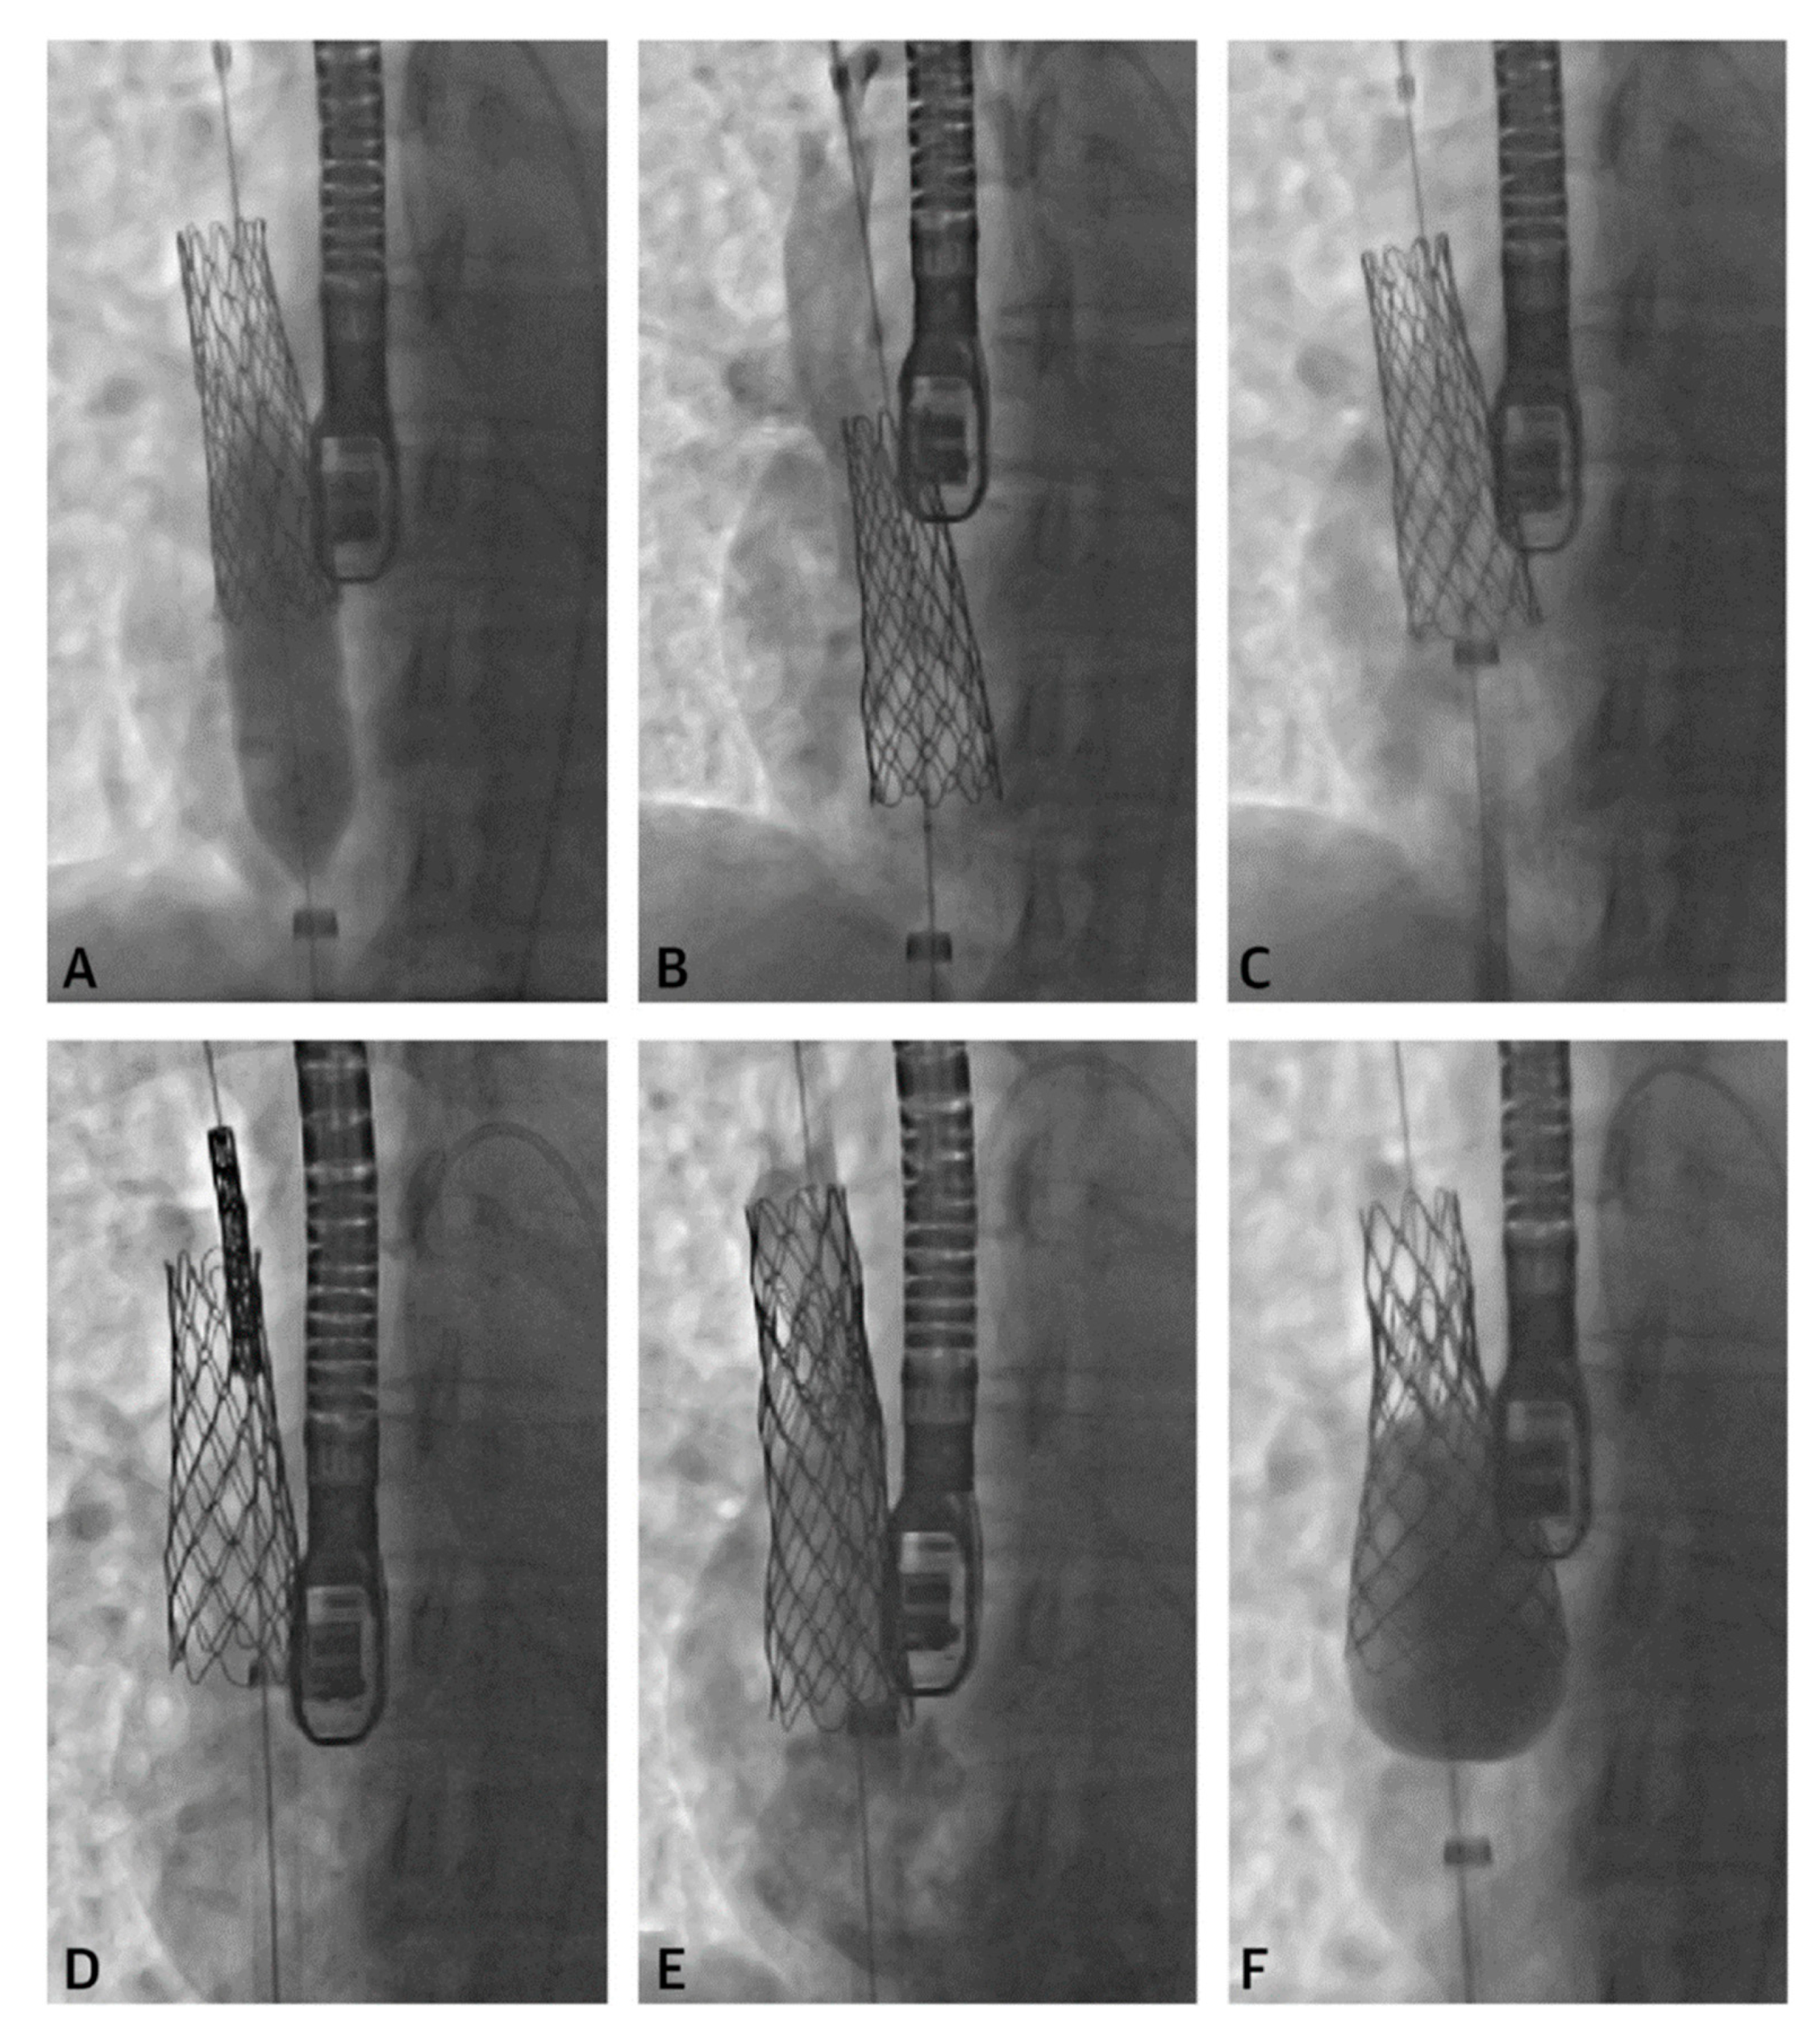

2.1. Sinus Venosus Atrial Septal Defect (SVASD)

- Hansen, J.H.; Duong, P.; Jivanji, S.G.; Jones, M.; Kabir, S.; Butera, G.; Qureshi, S.A.; Rosenthal, E. Transcatheter Correction of Superior Sinus Venosus Atrial Septal Defects as an Alternative to Surgical Treatment. J. Am. Coll. Cardiol. 2020, 75, 1266–1278. [Google Scholar] [CrossRef] [PubMed]

- Tandon, A.; Burkhardt, B.E.; Batsis, M.; Zellers, T.M.; Forte, M.N.V.; Valverde, I.; McMahan, R.; Guleserian, K.J.; Greil, G.F.; Hussain, T. Sinus Venosus Defects: Anatomic Variants and Transcatheter Closure Feasibility Using Virtual Reality Planning. JACC Cardiovasc. Imaging 2018, 12, 921–924. [Google Scholar] [CrossRef] [PubMed]